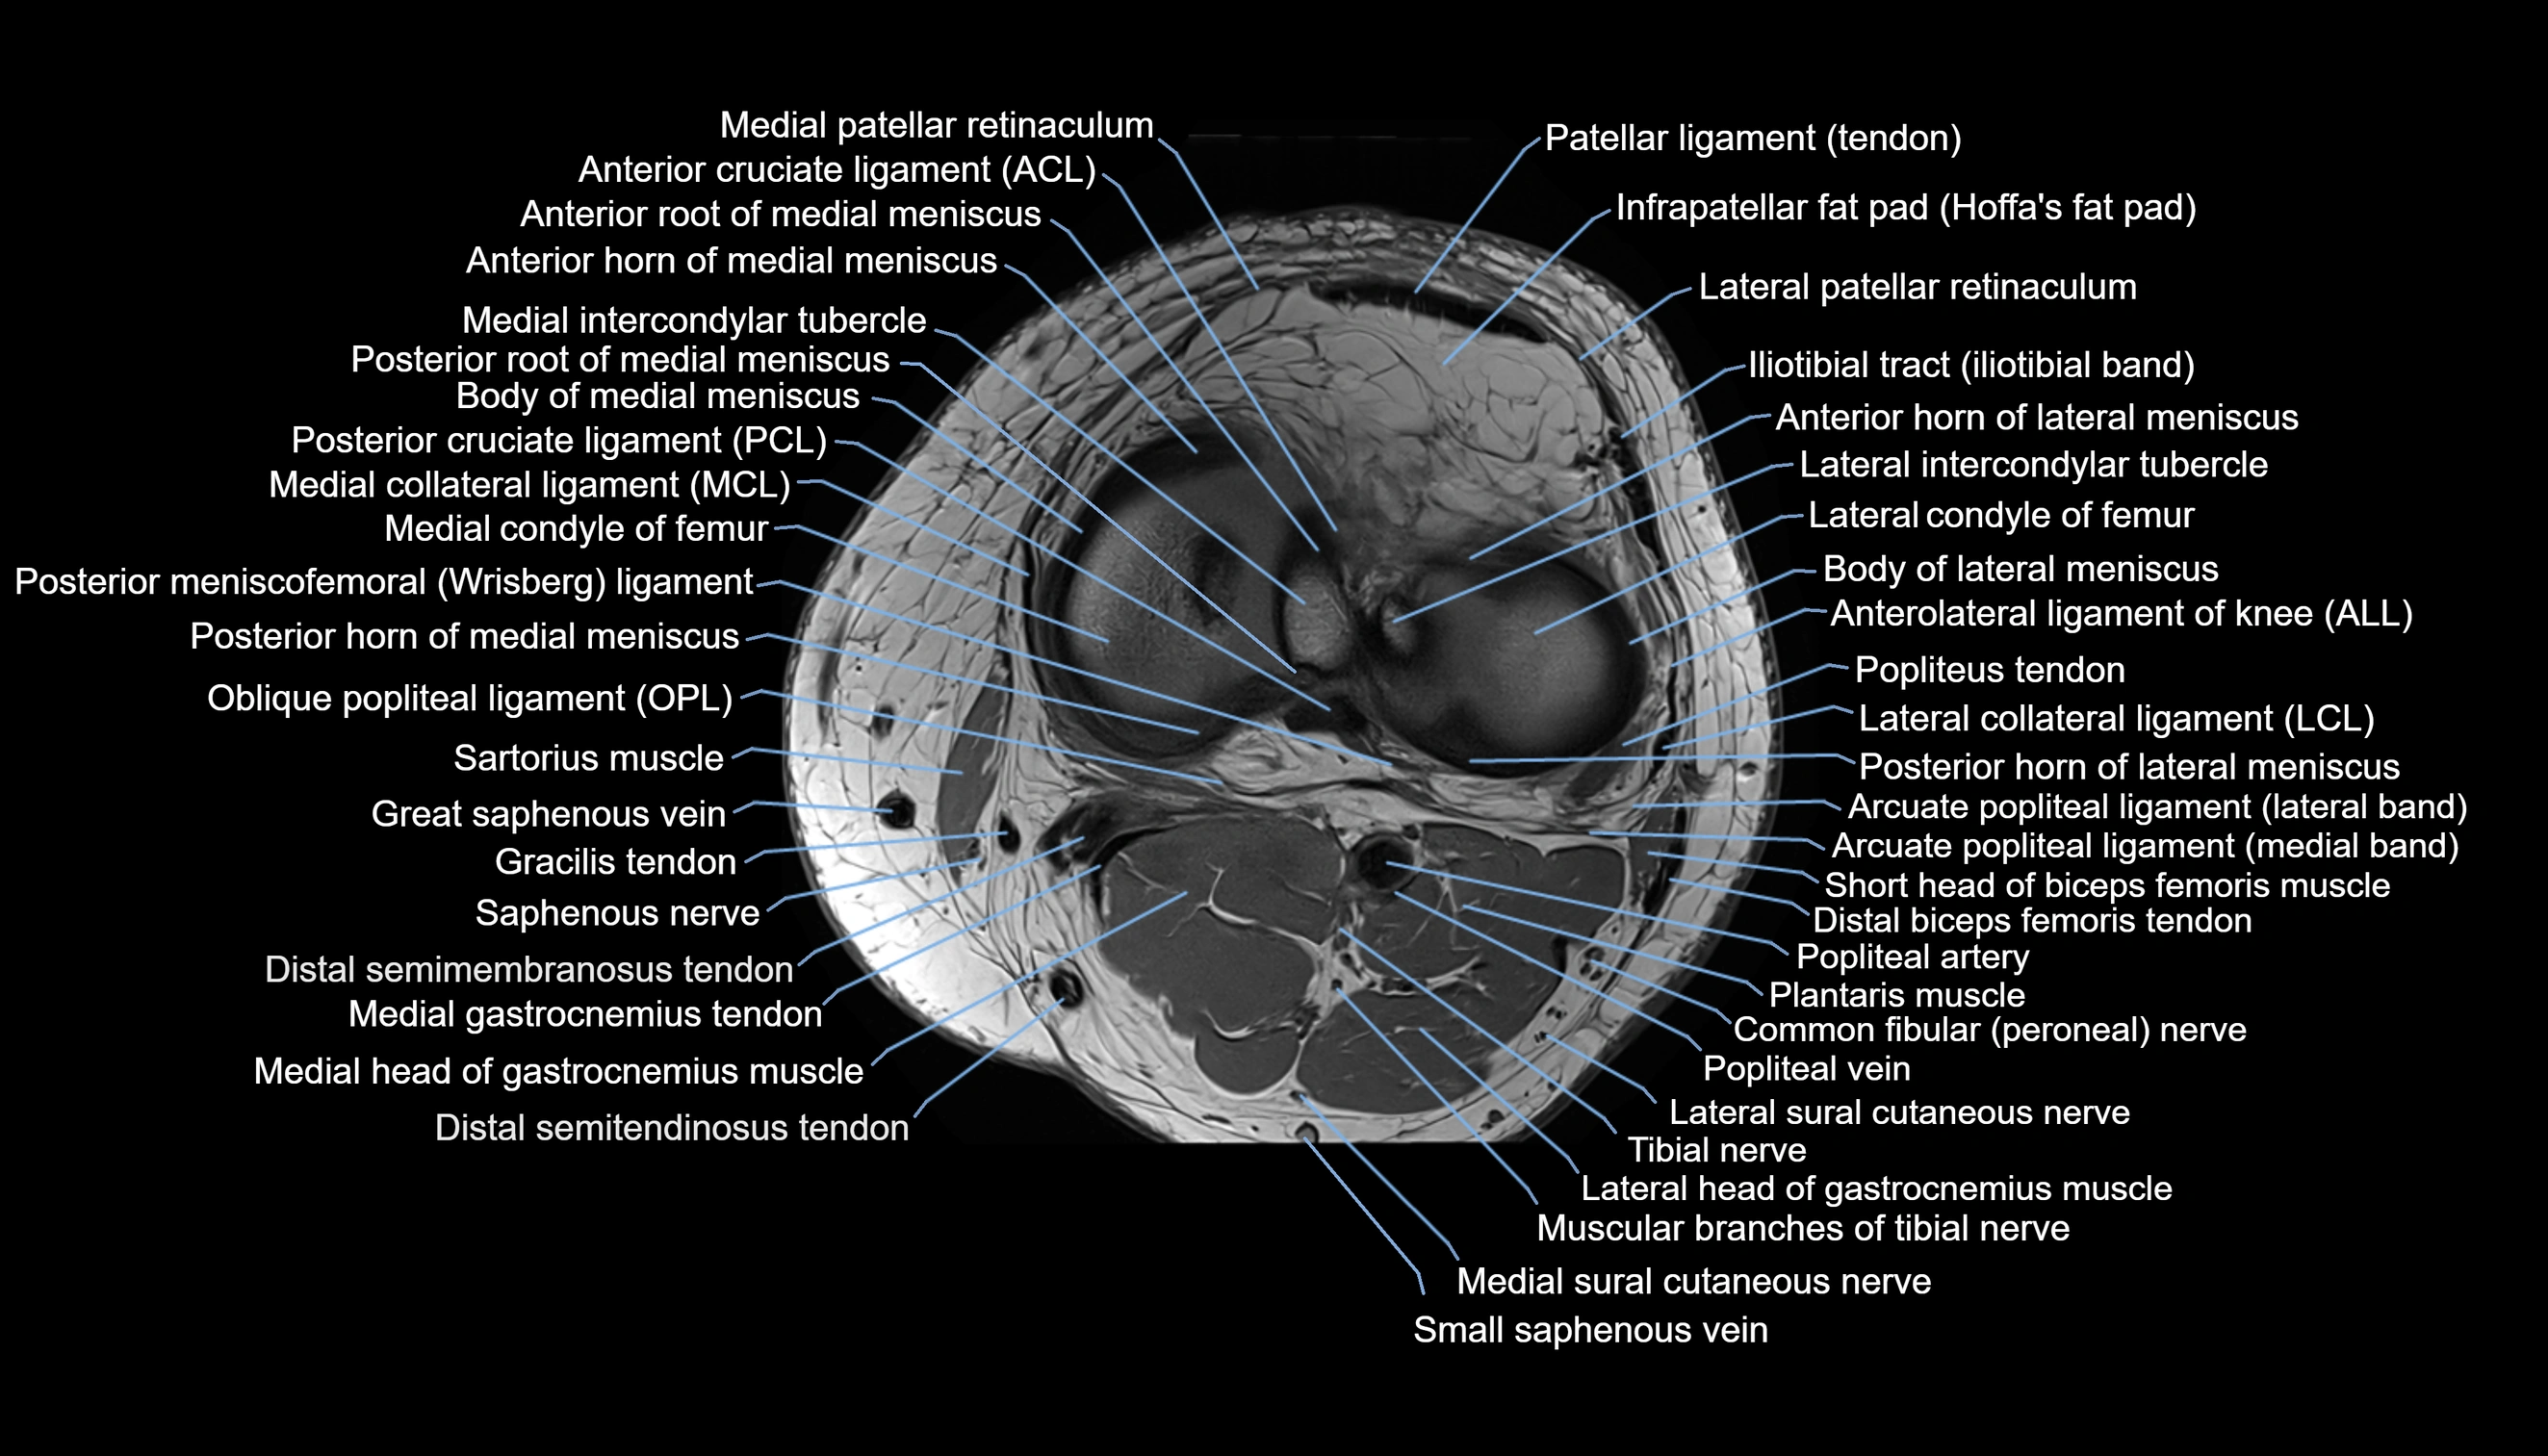

- Anterior cruciate ligament

- Anterior horn of lateral meniscus

- Anterior horn of medial meniscus

- Anterior root of lateral meniscus

- Anterior root of medial meniscus

- Anterolateral ligament of knee

- Arcuate popliteal ligament

- Body of lateral meniscus

- Body of medial meniscus

- Common fibular nerve

- Gracilis tendon (Distal)

- Lateral collateral ligament

- Lateral condyle of femur

- Lateral intercondylar tubercle

- Lateral patellar retinaculum

- Lateral sural cutaneous nerve

- Medial collateral ligament

- Medial condyle of femur

- Medial gastrocnemius tendon

- Medial head of gastrocnemius muscle

- Medial intercondylar tubercle

- Medial patellar retinaculum

- Oblique popliteal ligament

- Popliteal artery

- Popliteal vein

- Popliteus tendon

- Posterior cruciate ligament

- Posterior horn of lateral meniscus

- Posterior horn of medial meniscus

- Posterior meniscofemoral ligament

- Saphenous nerve

- Sartorius muscle

- Semimembranosus muscle

- Small saphenous vein

- Soleus muscle

- Tibial nerve